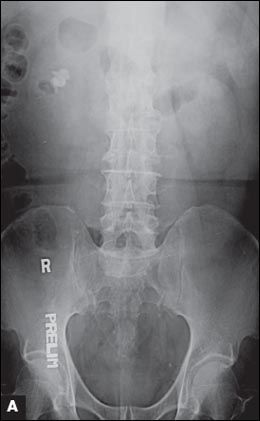

Figure 1 – A pretreatment plain radiograph reveals bilateral renal stones and a right lower ureteral stone inside an ureterocele (

A

). Treatment results are shown after the first percutaneous nephrolithotomy (PCNL) and removal of the ureteral stone (

B

) and after the second PCNL (

Urinalysis showed 5 to 10 white blood cells and 3 to 5 red blood cells per high-power field. Urine culture was negative. Plain radiography with a kidney-ureter-bladder (KUB) view revealed multiple opacities in the region of both kidneys and specifically in a location that corresponded to each renal pelvis (Figure 1A). A subsequent intravenous urogram (IVU) confirmed the presence of bilateral renal staghorn calculi and a right ureteral stone within a ureterocele. A radioisotopic study showed the differential function of the right and left kidneys to be 44% and 56%, respectively, with scarring in the upper pole of the right kidney. Serum calcium, phosphate, urate, blood urea nitrogen, creatinine, and electrolyte levels were normal.

The patient underwent transurethral incision of the right ureterocele and ureteroscopic removal of the ureteral stone. Simultaneous right percutaneous nephrolithotomy (PCNL) was performed, and a ureteral stent was inserted at the end of the procedure (Figure 1B). Second stage right PCNL for the residual stones was performed 2 weeks later, and all the stones were cleared (Figure 1C). Left PCNL was also performed with clearance of all the residual stones (Figure 1D). Stone analysis revealed that the calculi were composed of 76% magnesium ammonium phosphate (struvite) and 24% calcium carbonate apatite.